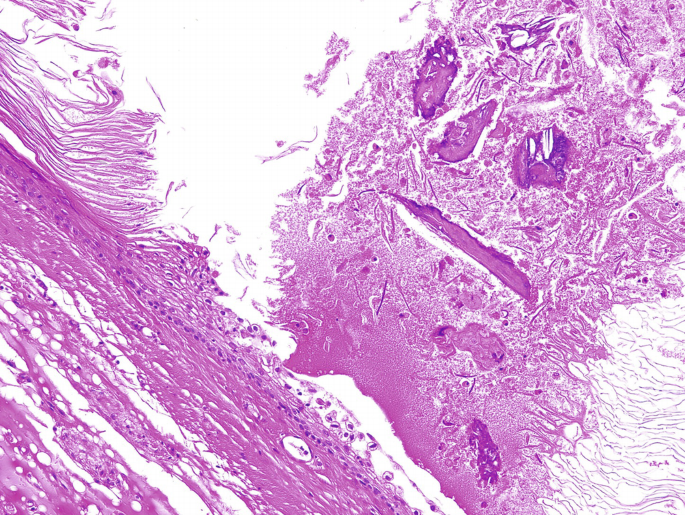

photomicrograph of a sectioned sebaceous gland Diagram - Quizlet Start studying photomicrograph of a sectioned sebaceous gland. Learn vocabulary, terms, and more with flashcards, games, and other study tools. Search - Course Hero C ezto.mheducation.com/hm.tpx 23. Label the photomicrograph of thin skin. Hair Sebaceous gland Dermis Hair Follicle Epidermis Duct of sebaceous gland KS ...

PreLab03a Integument & Prelab03b Integument Histology - Quizlet Label the photomicrograph of the skin and its accessory structures. epidermis hair follicle duct of sebaceous gland sebaceous gland.

Question: Label the photomicrograph of the sebaceous gland. - Chegg Label the photomicrograph of the sebaceous gland. This problem has been solved! You'll get a detailed solution from a subject matter expert that helps you learn ... Photomicrographs showing representative labelling of various skin... Sebaceous glands in hairy lower lip skin appeared in green as a result of nonspecific labelling by the streptavidin-Alexa 488 conjugate. SOLVED: Label tne photomicrograph Of the Skin and Its accessory ... So that would be the epidermis. Next here, the second one is the duck of the sebaceous gland or the oil glands. So this sebaceous gland produces the sabam or ...

Label the photomicrograph of the sebaceous gland.. Light Micrograph of a Sebaceous Gland and an Arrector Pili Muscle ... Please describe! how you will use this image and then you will be able to add this image to your shopping basket. Light Micrograph of a Sebaceous Gland and ... Highly Persistent Label-Retaining Cells in the Hair Follicles of Mice ... No label-retaining cells were found in the hair canal, sebaceous gland, or hair germ. ... Photomicrographs of a follicular label-retaining cell (LRC) 14 mo ... Label the photomicrograph of thin skin. Dermis Duct of sebaceous ... Label the photomicrograph of thin skin. Dermis Duct of sebaceous gland Hair Follicle Sebaceous gland Hair Epidermis. 1. See answer. plus. Add answer+10 pts. Label the photomicrograph of the skin and its accessory structures Accessory structures of the skin include hair, nails, sweat glands, and sebaceous glands. These structures embryologically originate from the epidermis and ...

Label tne photomicrograph Of the Skin and Its accessory structures,  Sebaceous gland, Duct ofl, sebaceous gland, Epidermis, Hair follicle